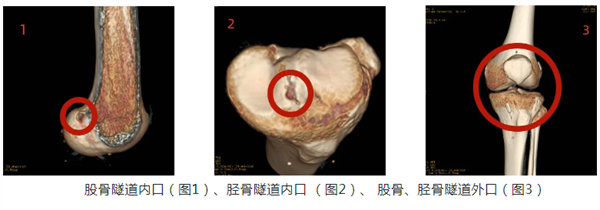

全內重建技術是指采用可翻轉鉆翼倒打鉆制作半長股骨、脛骨隧道,將編織好兩端已掛上可調節袢鋼板的移植肌腱從膝關節鏡的前內入路引入至股骨和脛骨隧道,最后兩側收緊可調節袢鋼板,從而將肌腱移植物分別固定于脛骨、股骨表面。

傳統的關節鏡下ACL重建方式是全長脛骨隧道ACL重建,其存在移植物要求高(長度和直徑)、骨質損傷大、內固定不牢固等技術缺陷;ACL全內重建技術兩個主要特征是采用雙側半長骨隧道和襻鈦板懸吊固定,具有降低手術創傷、節省肌腱、保留骨量和增強固定強度的優勢,被認為是目前最符合國人解剖特點和重建需求的ACL重建術式之一。